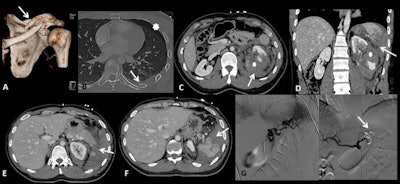

A 26-year-old male sustained a high-speed fall on his left side against rocks. 3D reconstructed CT image shows a distal third clavicular fracture (arrow in A). Axial CT image in lung window shows posterior rib fracture (arrow in B) and left anterior pneumothorax (asterisk in B). Contrast-enhanced CT images in axial (C, E, F) and coronal planes (D) show a wide laceration of the left kidney (asterisk in C and D) associated with perirenal hematoma (arrow in C), a contusion of the pancreatic tail (arrow in E), and a grade IV splenic injury (arrows in D, F). Angiography (G) performed on the same day shows inhomogeneous opacification of the spleen without any sign of active bleeding; main splenic artery embolization was performed with coils (H).

A 26-year-old male sustained a high-speed fall on his left side against rocks. 3D reconstructed CT image shows a distal third clavicular fracture (arrow in A). Axial CT image in lung window shows posterior rib fracture (arrow in B) and left anterior pneumothorax (asterisk in B). Contrast-enhanced CT images in axial (C, E, F) and coronal planes (D) show a wide laceration of the left kidney (asterisk in C and D) associated with perirenal hematoma (arrow in C), a contusion of the pancreatic tail (arrow in E), and a grade IV splenic injury (arrows in D, F). Angiography (G) performed on the same day shows inhomogeneous opacification of the spleen without any sign of active bleeding; main splenic artery embolization was performed with coils (H).Injury prevention strategies should focus on improving riders' technique, trail conditions, and protective equipment, they added. The use of protective equipment is of crucial importance, and a full-face helmet -- like those used in motorcycling that include a horizontal bar to protect the lower face -- is probably the most important and nearly universally adopted piece of safety gear for downhill biking.